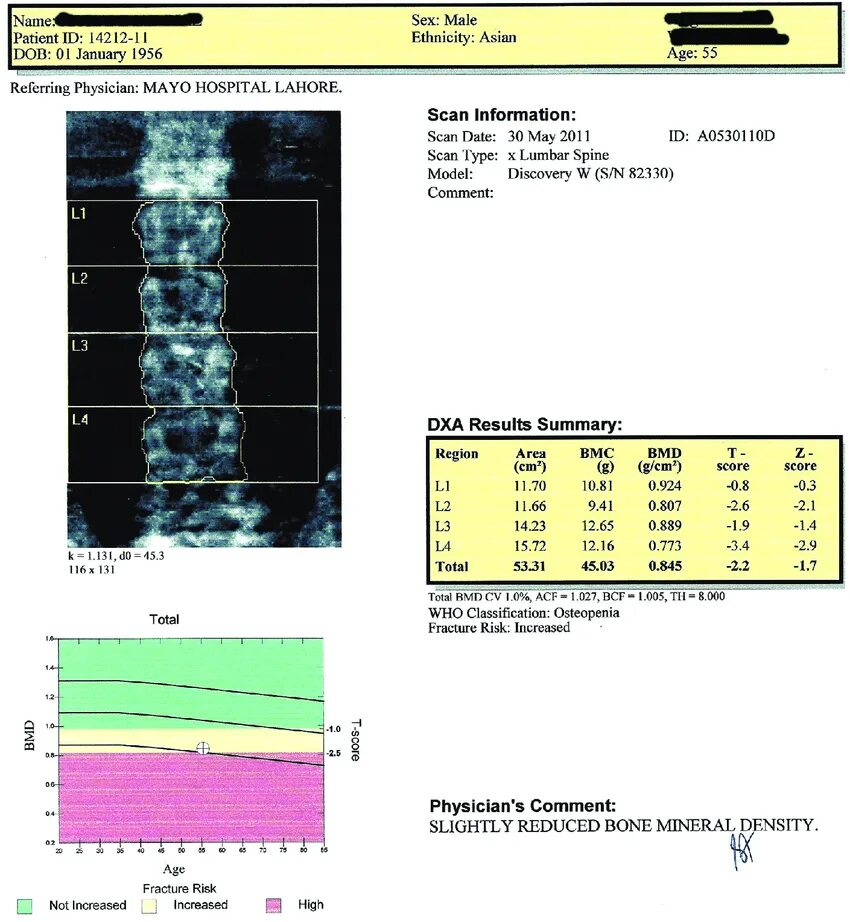

Scan means